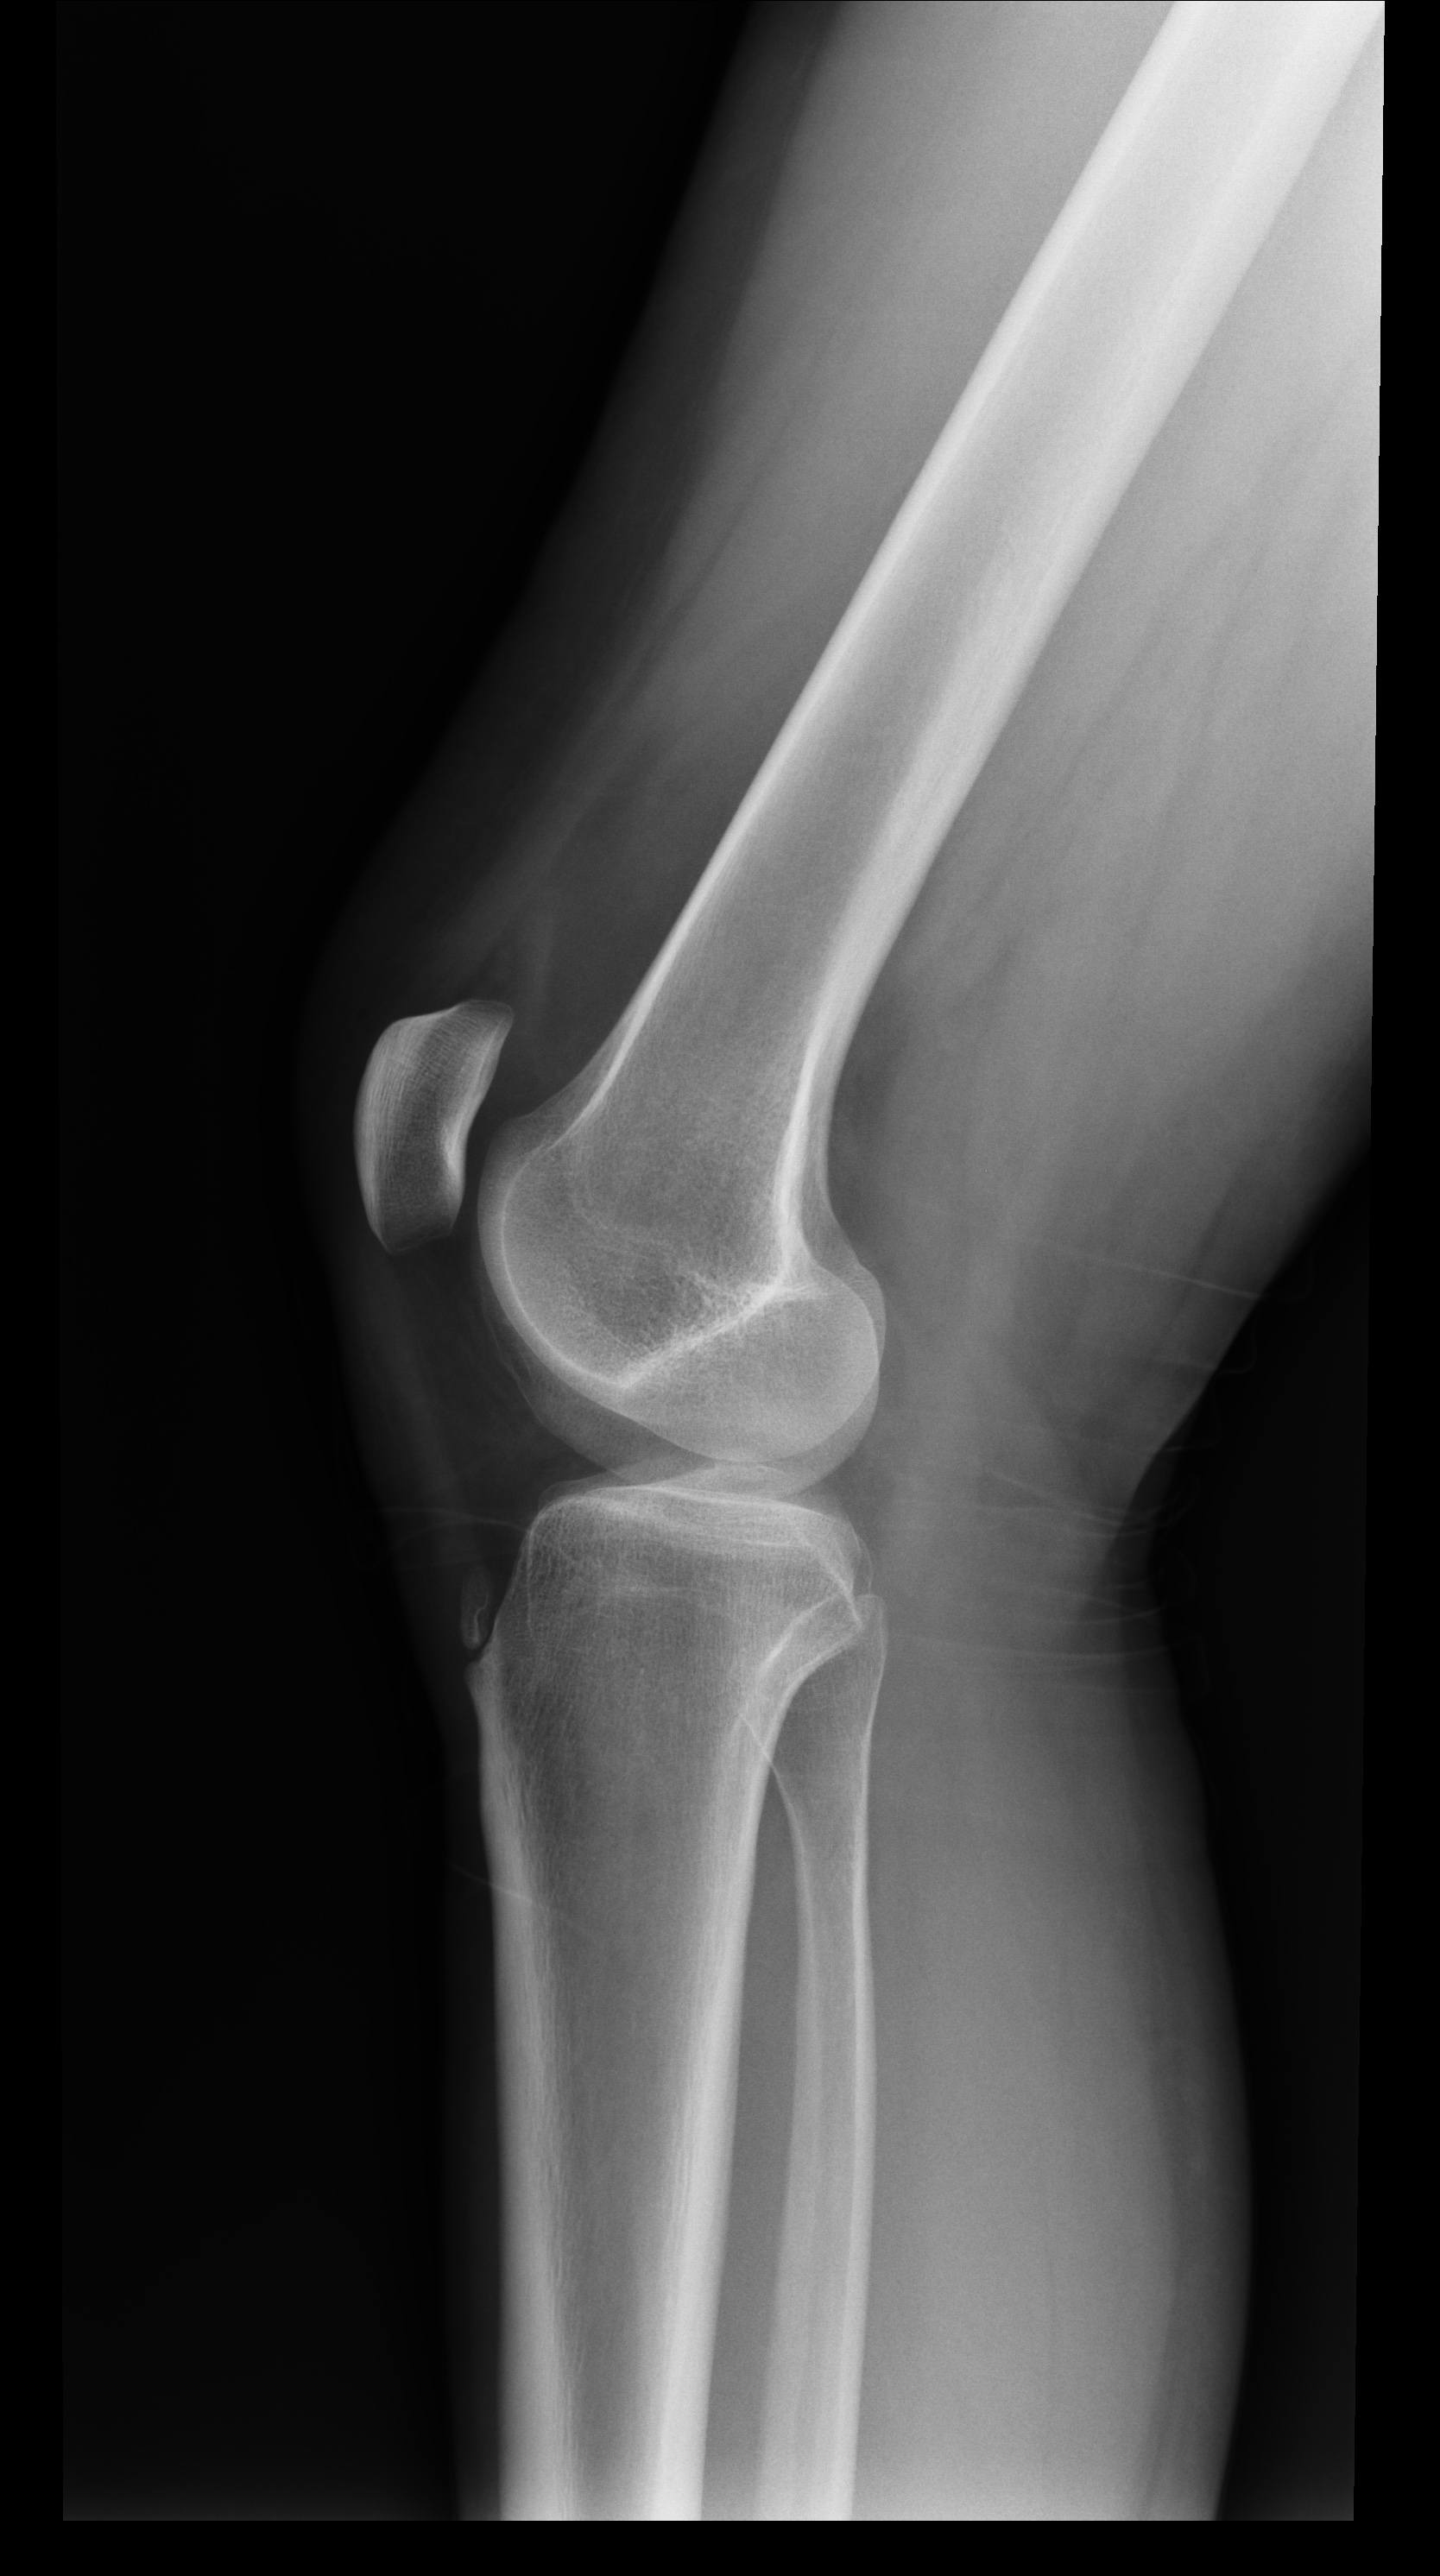

Paciente jóven que sufre un traumatismo al golpearse en la rodilla con el marco de una puerta, lo cual le impide mantener el peso sobre el miembro inferior derecho.

defecto de osificación del tubérculo tibial. No debemos confundir con rotura.